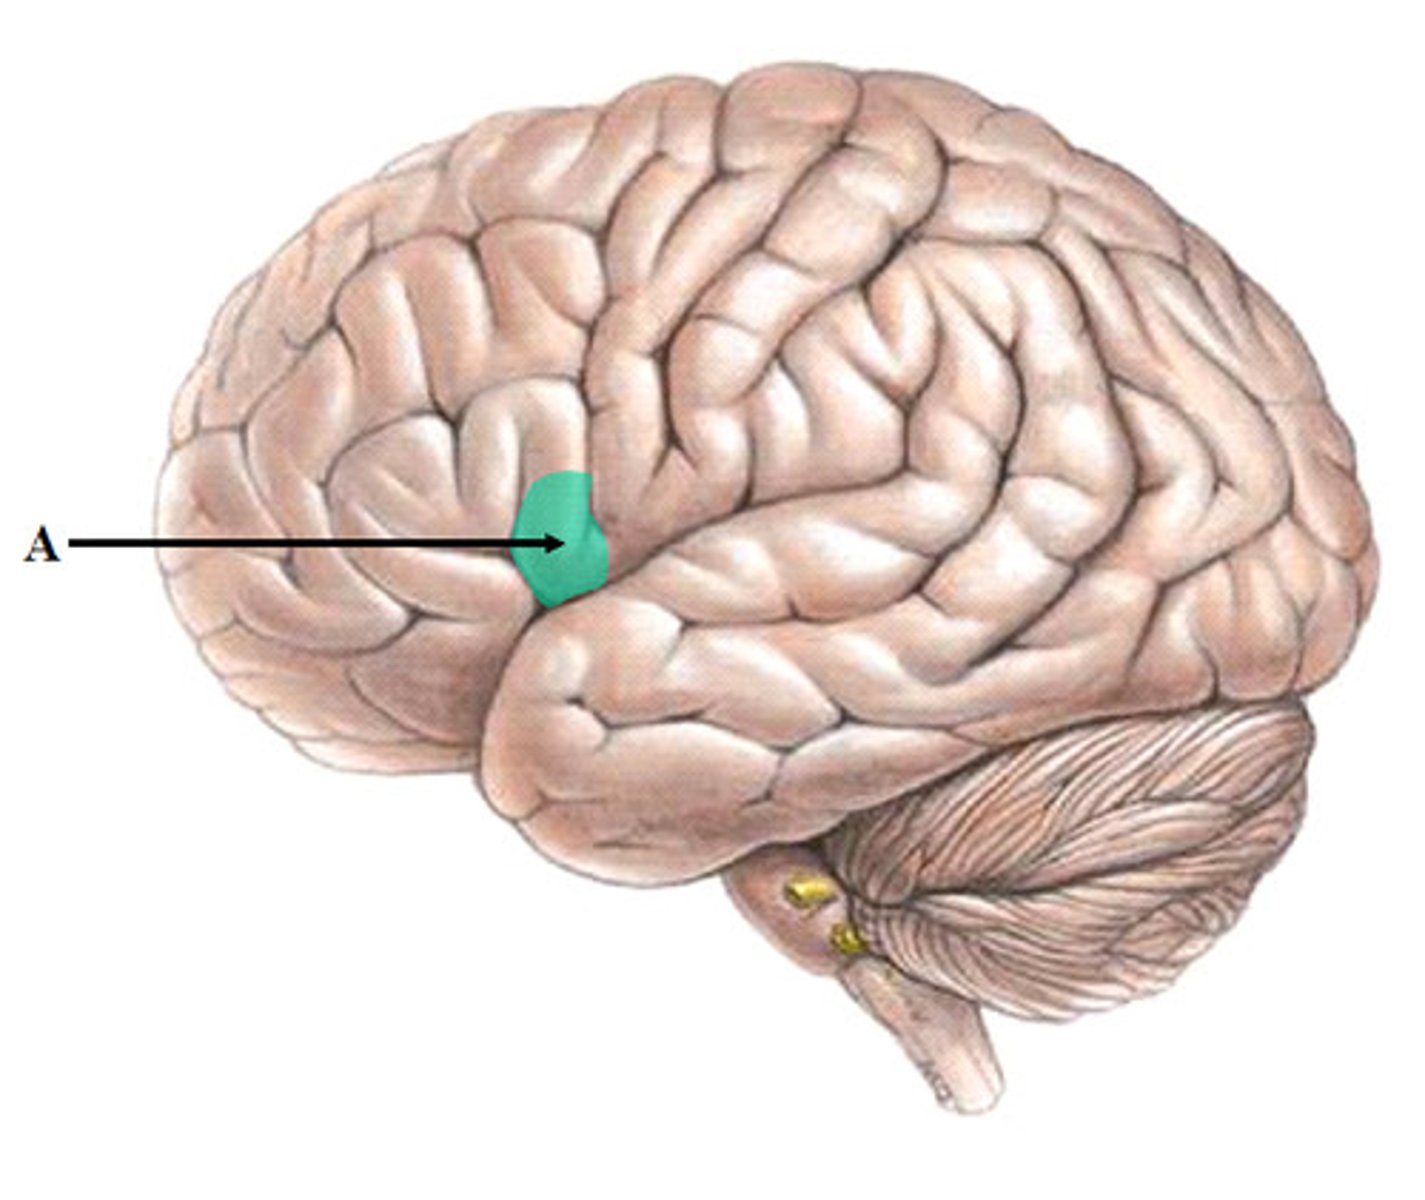

Broca's area

the language expression area in the frontal lobe (usually in the left hemisphere) that directs the muscle movements involved in speech